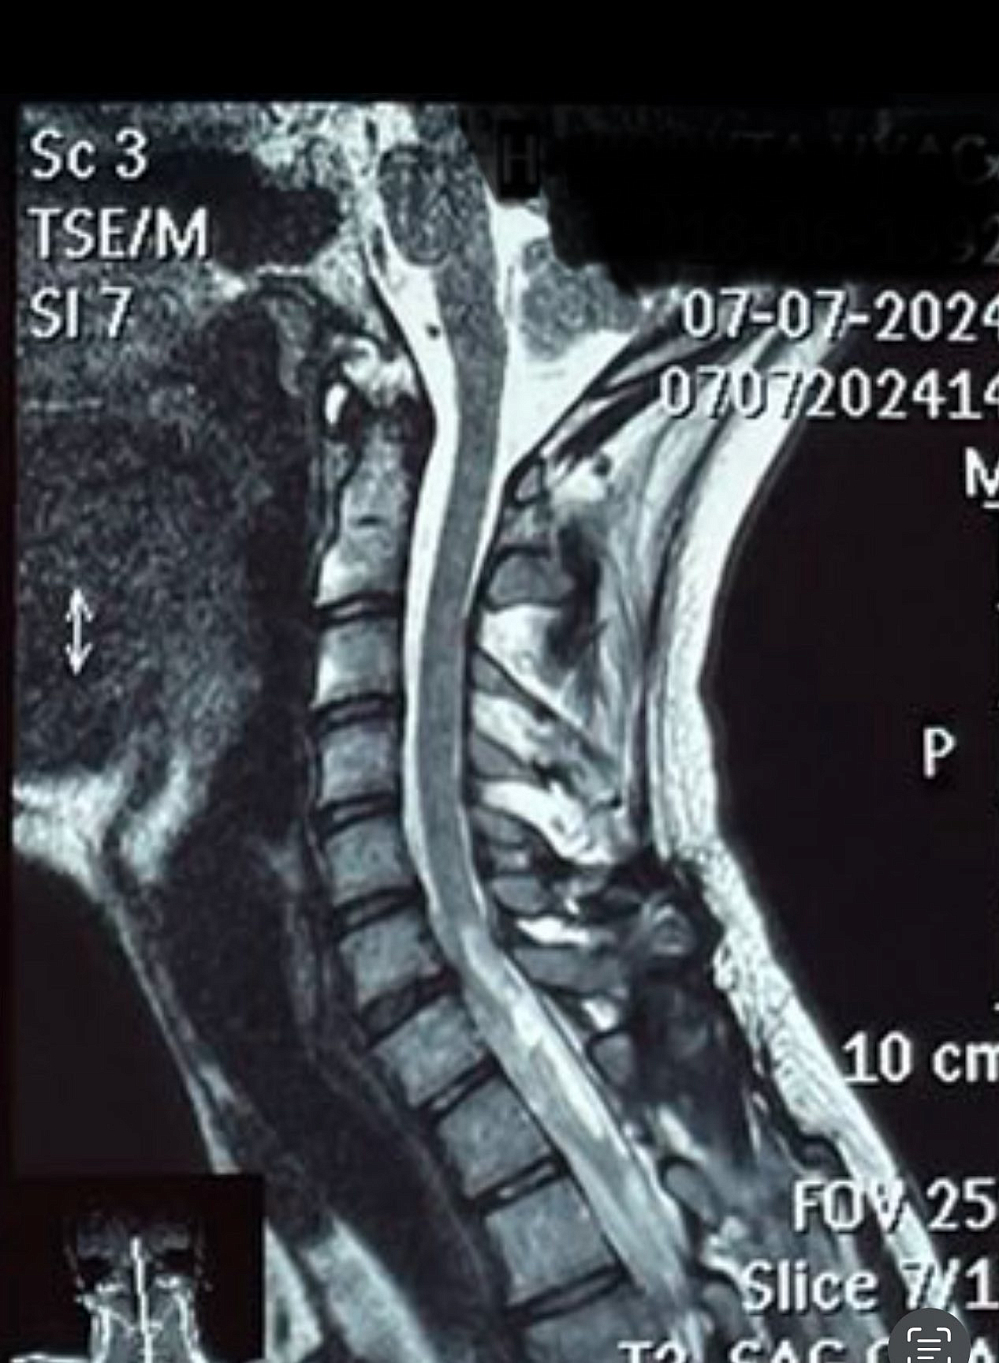

Як ви думаєте, про що ці фігурки, створені руками тяжкопораненого захисника України з вогнепальним ушкодженням шийного відділу хребта і спинного мозку?

Вірно! Про найскладніше — про відновлення дрібної моторики і сенсорики пальців рук.

Коли після повної знерухомленості вже вдається виконувати декілька кроків з підтримкою ортезів та асистентів — це велика перемога.

Але повернути точність рухів пальців, відчути дотик, вагу, текстуру предмета — це один з найвищий щаблів відновлення після шийного ушкодження.

За кожним таким рухом — понад 2000 годин послідовних занять, процедур і тренувань.

Ці фігурки — не просто вироби. Це результат колосальної спільної роботи, основаної на прихованих можливостях нервової системи і психіки людини, її віри в те, що контроль і відчуття можуть повернутися.